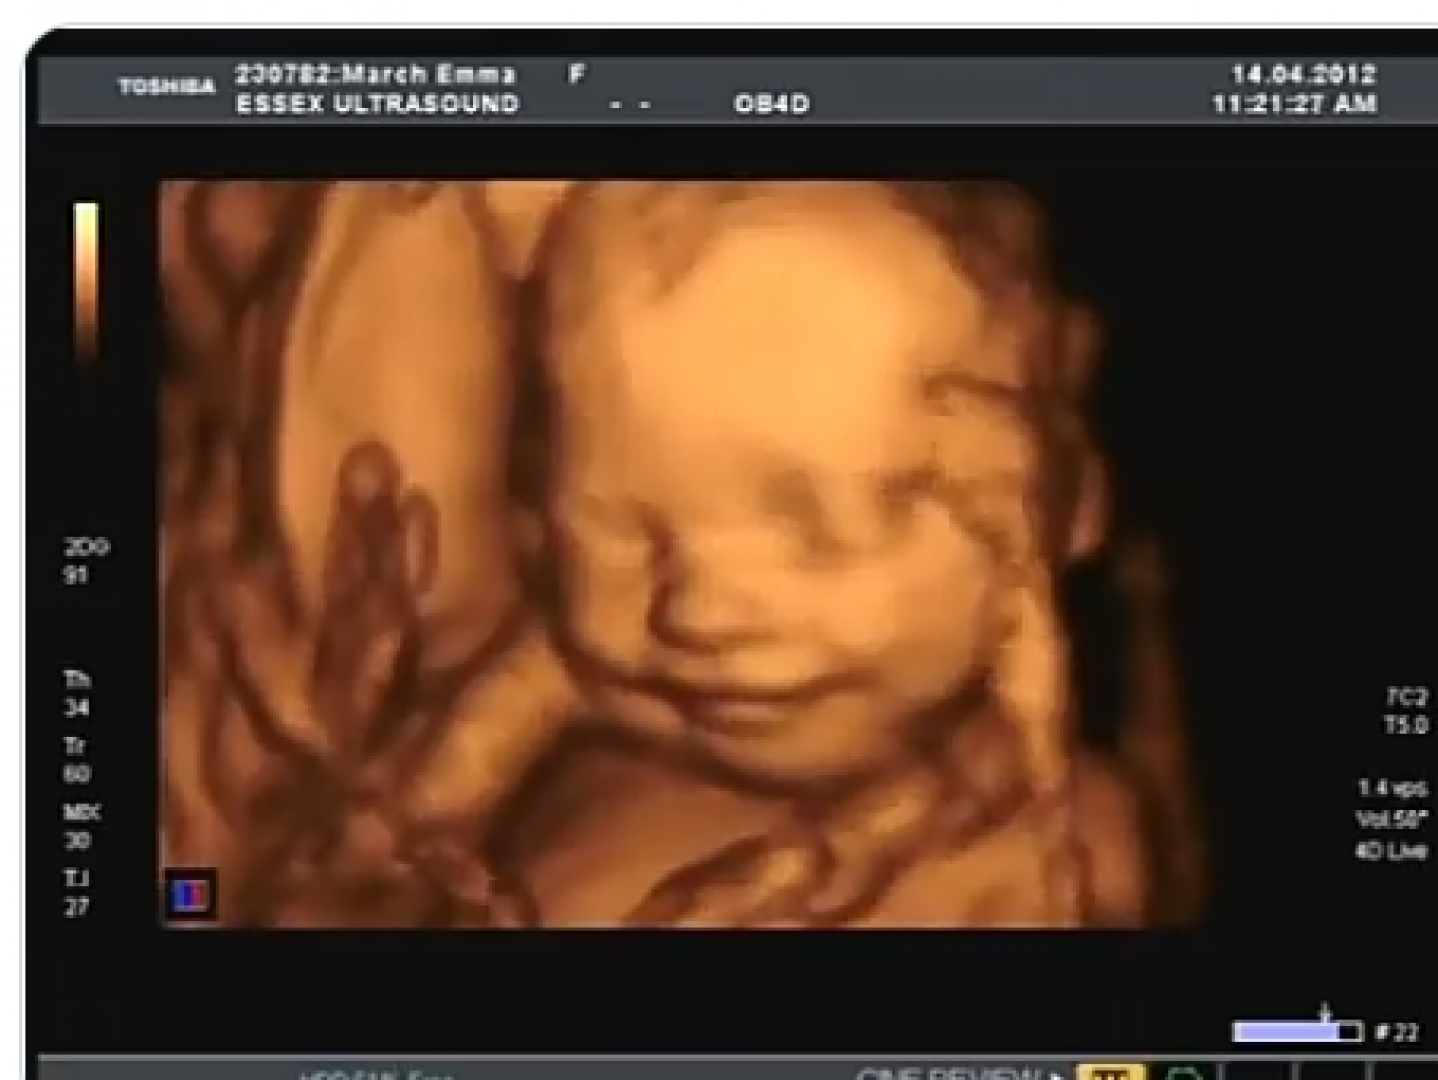

• بالرغم من صغر حجم قلب الجنين في هذه المرحلة، فإنه ينبض بشكل مستمر ويتحرك لضمان تدفق الدم إلى كل أجزاء الجسم، ويتم قياسه باستخدام جهاز فحص الأشعة فوق الصوتية.

• يجب أن يتم هذا الفحص خلال زيارات الحمل المستمرة في هذه المرحلة، ويتم حتى الآن تحديد المعدل الطبيعي لنبضات الجنين الذي يجب أن يكون بين 120 -170نبضة في الدقيقة.

• بداية من الأسبوع السادس حتى الأسبوع التاسع، تستطيع الأم فحص طفلها للتأكد من سلامته عن طريق التصوير الإشعاعي والموجات الصوتية للاطمئنان على نبض الجنين.